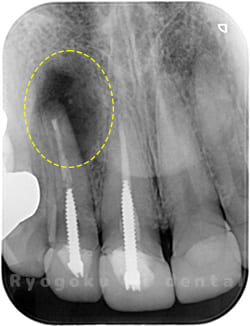

Case02

- 原因

- 慢性根尖性歯周炎

- 治療期間

- 1回(消毒・洗浄も含めると3回)

- 治療内容

- 歯根端切除術

- 治療費用

- ¥110,000

他院で抜歯と判断され、インプラント治療を提案された患者様です。被せ物を外さずに、歯の根尖部に外科的にアプローチし、病気の部分を除去しました。

<リスク・副作用>

外科手術のため、術後に出血、痛みや腫れ、違和感を伴います。口腔内の状態によっては適応できないことがあります。歯根端切除で治らなければ抜歯を検討しなくていけない場合もあります。